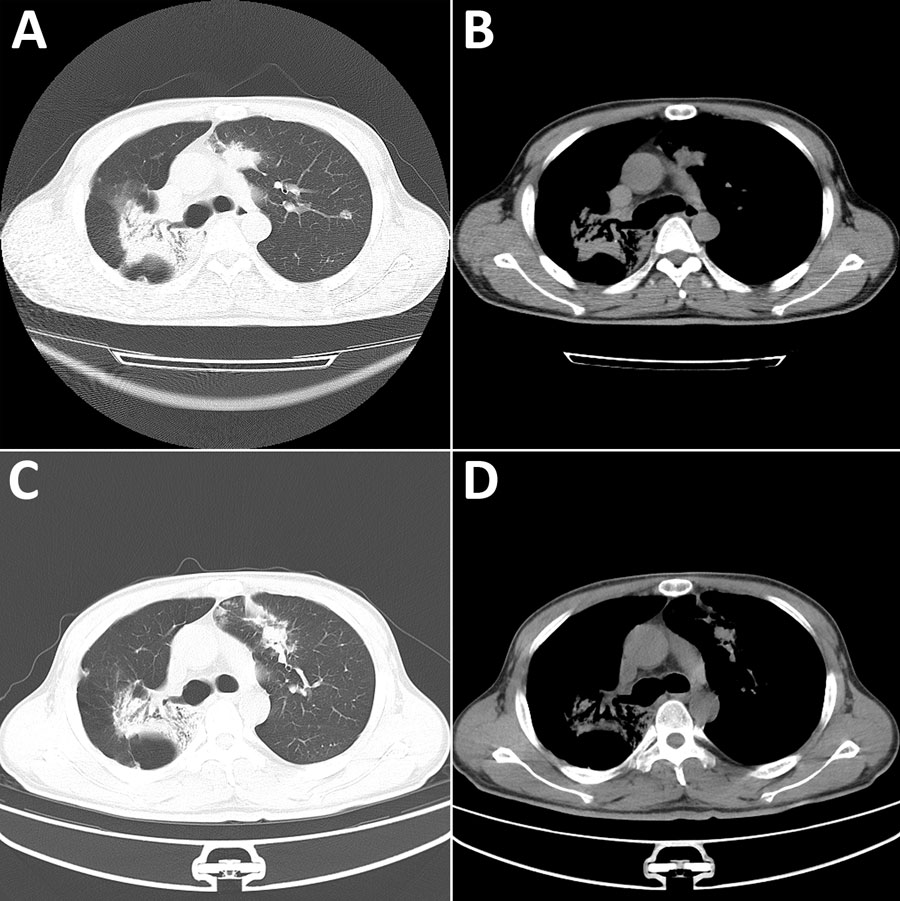

Figure 1. Chest computed tomography (CT) images from a patient with disseminated blastomycosis mimicking tuberculosis, China. A, B) Chest CT at first admission revealed bilateral lobar infiltrates (A) and patchy opacities (B). C, D) Chest CT taken 2 months later showed resolution of left lung lesions but progression of right lung lesions.